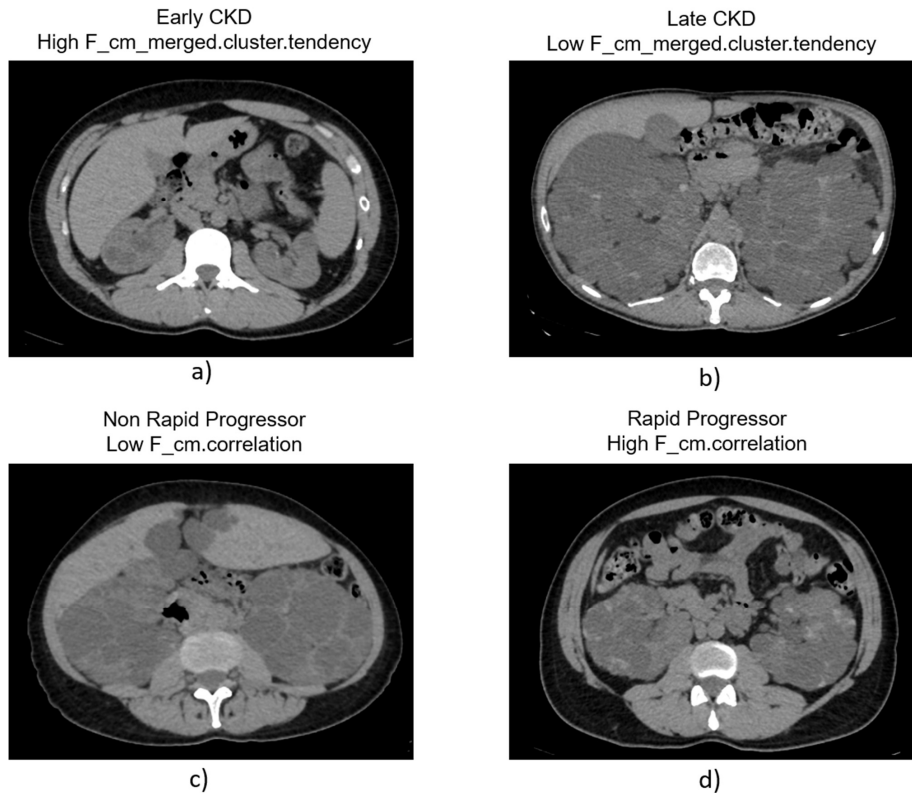

研究首先验证了影像组学对基线肾功能的预测价值。通过Wilcoxon检验筛选出84个显著特征,其中聚类趋势特征(F_cm_merged.clust.tend)表现最佳。该特征与年龄组成的模型AUC达0.91,敏感性0.82,特异性0.90,优于传统ht-TKV指标。影像显示,早期CKD患者(

在预测疾病快速进展方面,相关性特征(F_cm.corr)展现出突出价值。该特征反映肾脏实质的纹理异质性,在快速进展组显著升高(p=0.04)。基于此建立的模型AUC为0.78(95%CI 0.65-0.90),敏感性高达0.92,显著优于ht-TKV模型(AUC 0.65)。